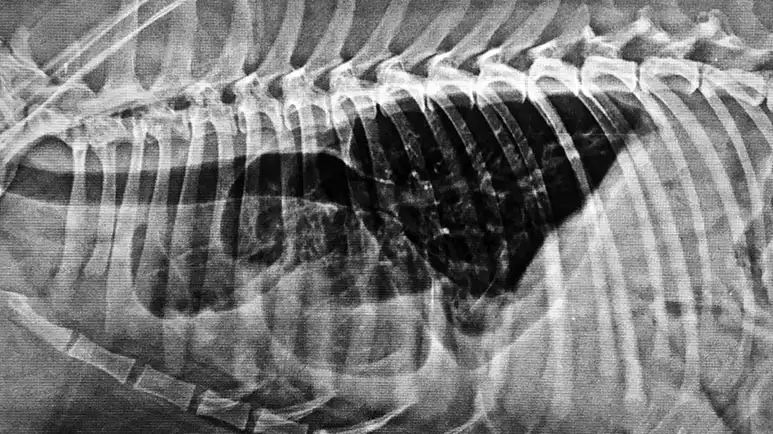

In animals, the thoracic cavity is a vital space located in the upper chest. Like us, this area houses the heart, lungs, and other essential organs, such as the windpipe for your beloved pet.1 As such, the thoracic cavity is crucial to supporting life, but under certain (and sometimes unknown) circumstances, it can develop an uncommon condition known as chylothorax.

Chylothorax is a condition wherein chyle, a milky liquid of small fat molecules, accumulates in the thoracic cavity.2 While it’s uncommon for household pets, cats are four times more likely to get it than dogs. Southpaws, an Australian emergency hospital for animals, summarizes the role of chyle in pets below:3

What happens when chyle builds up the pleura in the thoracic cavity? According to the American College of Veterinary Surgeons, the accumulation of chyle will cause difficulty in breathing. Moreover, it will cause many metabolic problems and weaken the pet’s immune system because it doesn’t pass through the proper pathways as it contains protein, white blood cells, and other nutrients. Finally, chyle irritates the pleura and pericardium, which leads to inflammation.4